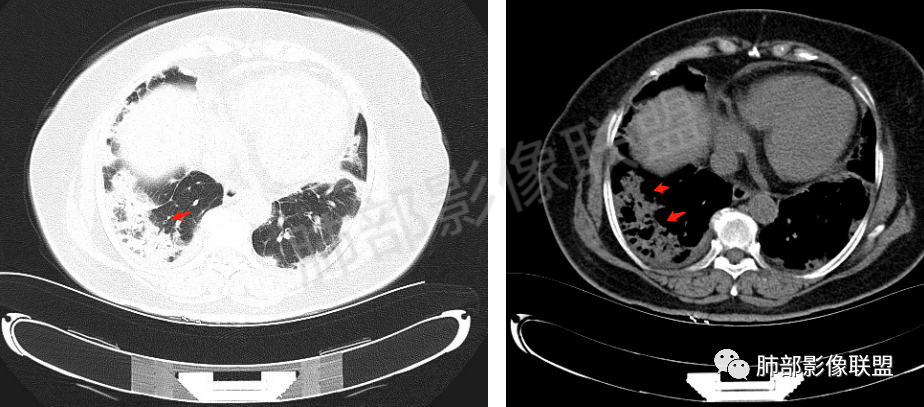

双肺下叶胸膜下为主实变并渗出影,胸膜下清楚,无骨受累,病灶中心空腔或未完全实变区域,双肺分布,患者农民,亚急性病程,I型呼吸衰竭,低蛋白血症,考虑亚急性感染性肺病所致,需详细追问病史,近期接触史,居住环境,病原菌考虑努卡菌,放线菌可能,部分少见真菌。

老年女性,咳嗽咳痰伴气急20余天,有皮炎数月,CRP,血沉高,PCT略高,CEA高,血糖稍高,CEA高,缺氧,尿蛋白及尿白细胞高,G试验阳性,GM临界阳性。影像表现:双肺胸膜下为主多发斑片状及结节样实变影,支气管扩张表现为主,部分支气管直达远端,部分中断于实变影中部。影像初步诊断为双肺OP样改变。临床分析:一、感染性疾病1、隐球,亚急性渐进性加重病程,有皮炎史,CRP,血沉高,PCT稍高,GM试验临界阳性都可以支持,影像表现也可以支持。但一般G试验为阴性,此例阳性,加上灌洗液未找到依据,有疑问。需要查隐球荚膜抗原或NGS。2、曲霉,临床表现及G试验和GM试验支持,但影像表现不算典型表现。可能稍小。二、非感染性疾病1、风湿相关性间质性肺炎,双肺胸膜下多发OP样改变,有皮炎史,有尿蛋白增高,灌洗液病原体检测阴性。要考虑,但此患者70多岁,无吸烟史及职业史,亚急性发病,双肺改变以实质受累为主,没有明显的间质受累的细网格表现,也存疑,需要查相关抗体。2、CEP,灌洗液没有提嗜酸情况,除非故意隐瞒,否则不太支持。3、血管炎,有尿蛋白改变,但影像不支持,ANCA阴性也不支持。4、COP,目前依据不是太足。三、肿瘤性病变。肺炎型肺癌,老年女性,CEA增高,加上右肺胸膜下改变,要想到,但分布太广泛,病史太短,没有增强表现,没有以前的老片对照,灌洗液也没有提找到肿瘤细胞,直接诊断还是依据不足。综上,考虑感染性疾病(隐球或曲霉)>风湿相关性结缔组织疾病>肺炎型肺癌(粘液腺)。

2、影像特点:双肺胸膜下为主、多发斑片影、结节样实变影及磨玻璃样密度影,大部分病灶边缘平直、边界清,磨玻璃密度病灶内可见细网格影,部分病灶内可见支气管扩张表现,部分支气管直达远端,部分中断于病灶中部。部分病灶有侧向融合趋势。

3、病例小结:老年女性,咳嗽咳痰伴气急逐渐加重,入院后有低热。部分炎性指标升高,肺部片影,可以符合感染性病变,但是血培养、支气管灌洗液培养等检查无阳性表现。但仍影警惕隐球菌感染,患者临床表现相对轻微,胸膜下病灶,磨玻璃影等。